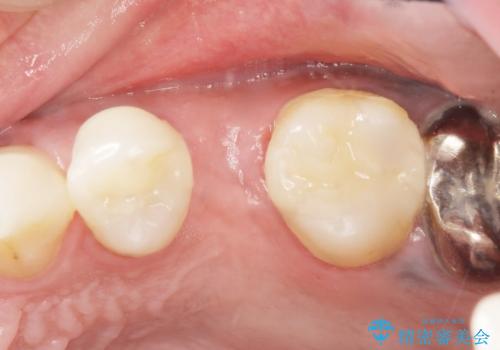

う蝕を丁寧に除去したのち、セラミックインレーによる修復を行いました。

インプラント埋入まで抜歯後(左上5)の骨の治癒を待つ間に、治療期間の短縮を図り先んじて両隣在歯(左上4,6)のインレー修復を行っております。

審美的な仕上がりと自然な咬み心地に喜んで頂けました。

インレーの種類:セラミックインレー(e-max press)